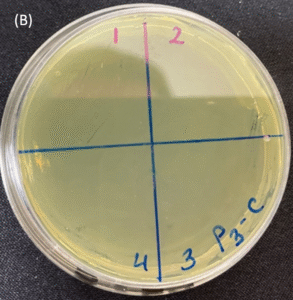

Photos of the Petri plates, 72 hours after bacterial (Pseudomonas aeruginosa) inoculation.

Image (B) is the control plate. The blue lines divide the plate into quadrants.